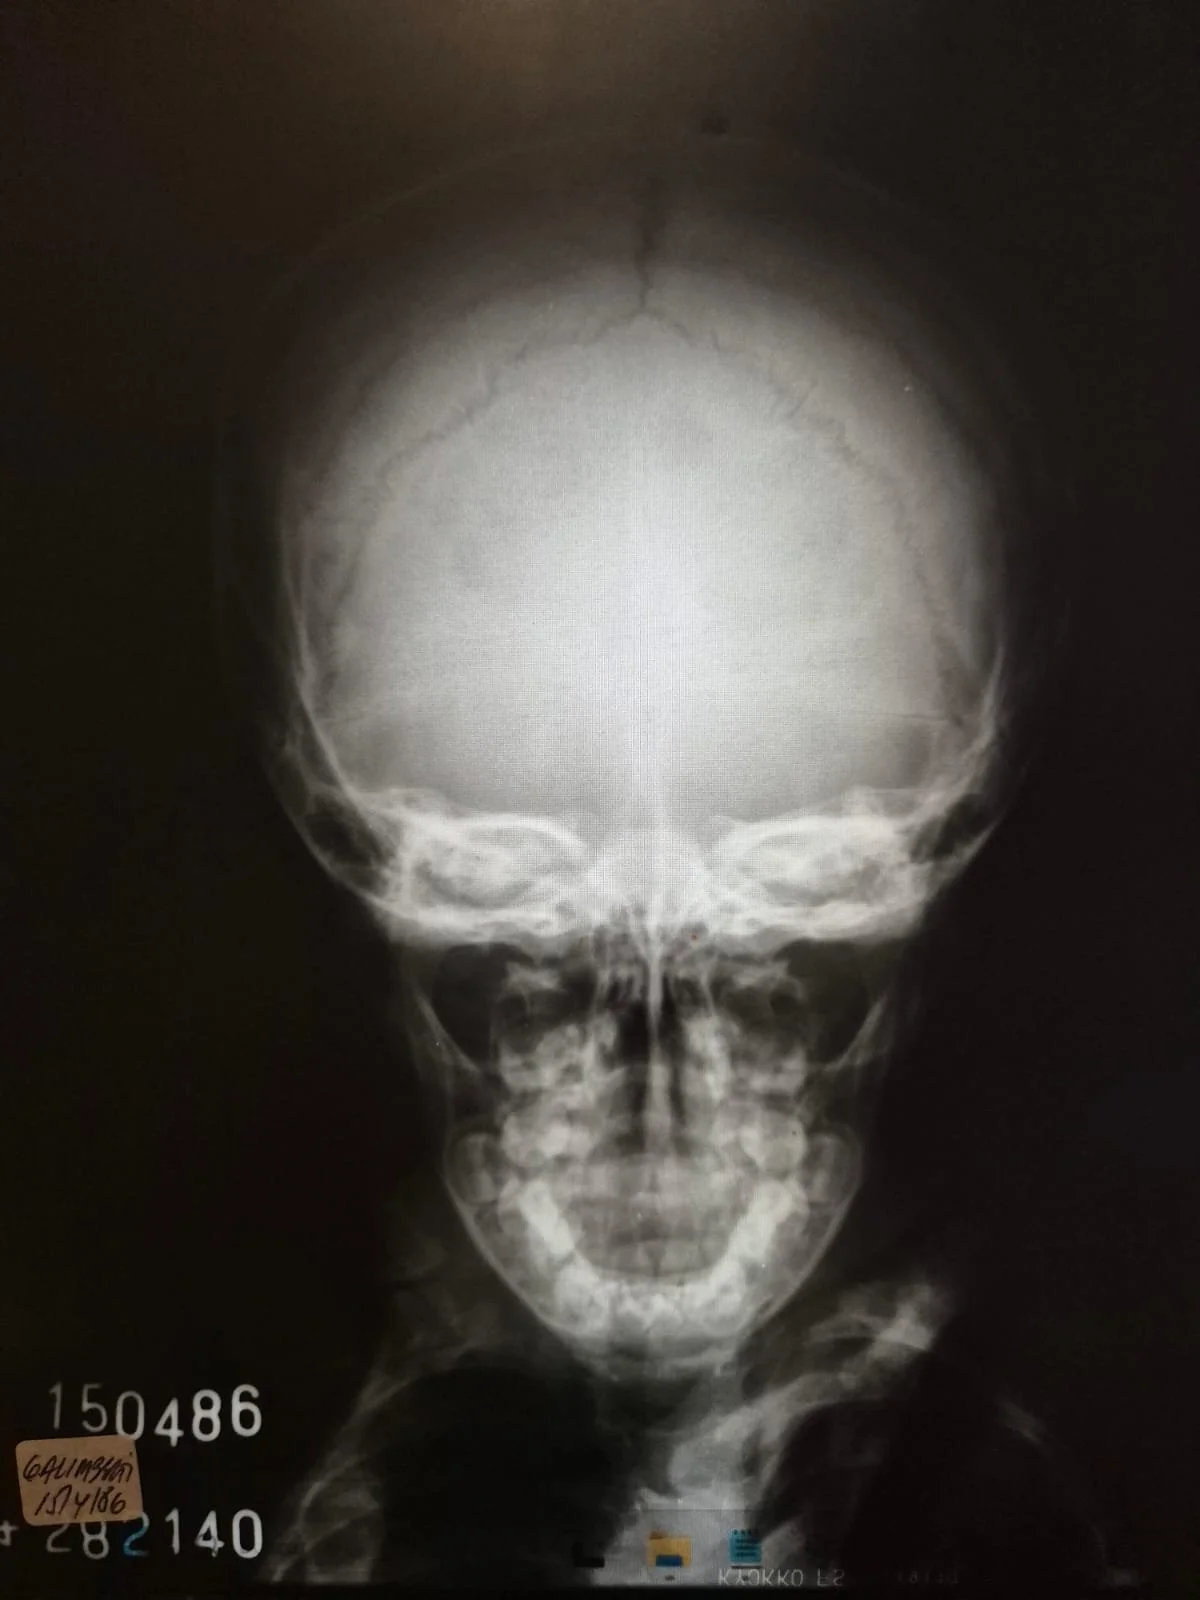

En esta obra tomo dos momentos extremos de mi vida: la caída que viví cuando tenía casi 2 años de edad y que dejó una fisura en mi cráneo, y la depresión que atravesé a los 35 años, llevándome a conocer lo más oscuro de mi existencia.